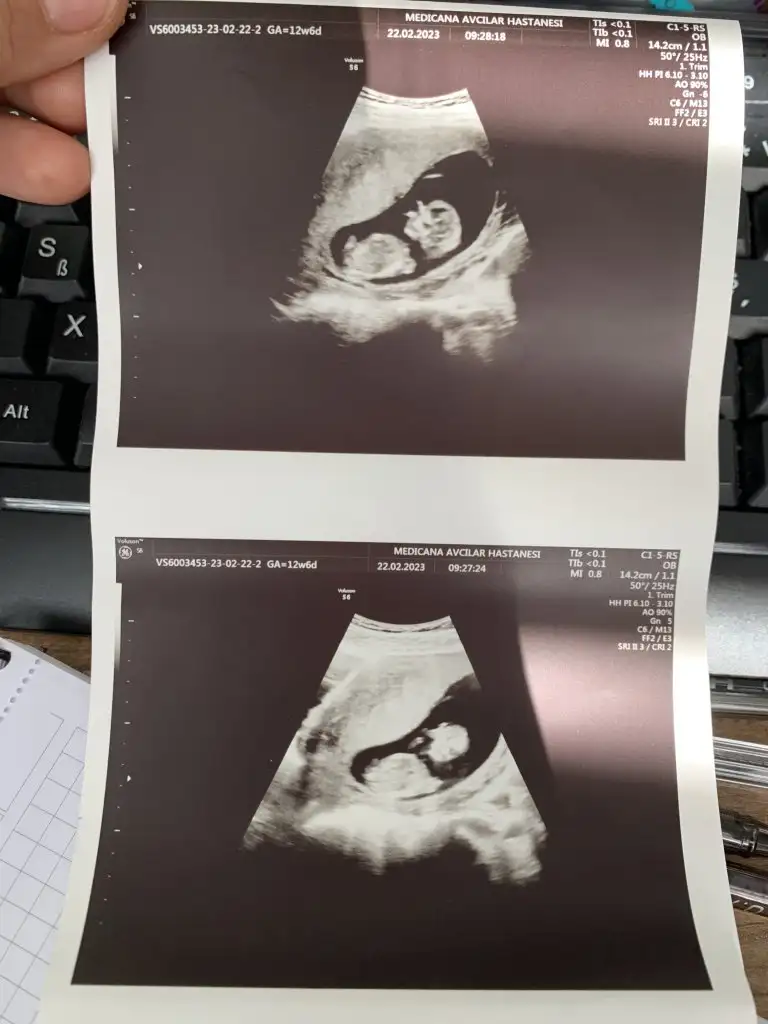

Kızlar bana da bakarmısınız

Sat a göre 12+4

Usg ye göre 13+3